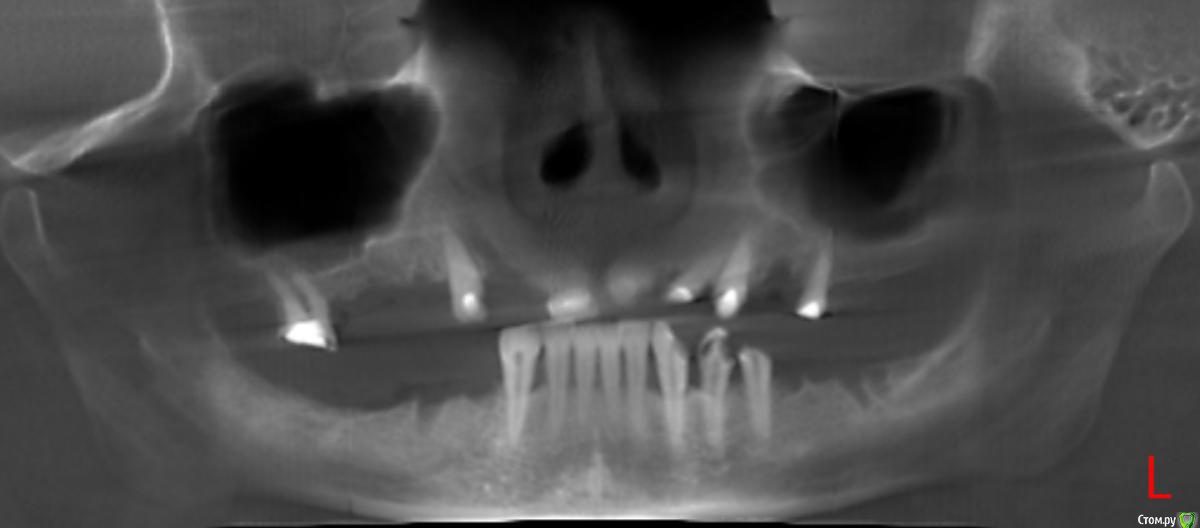

Ксени_Я Опубликовано 27 июня, 2015 Автор Поделиться Опубликовано 27 июня, 2015 (изменено) Bier и Alejandro, спасибо за ответы.Внесу ясность. Я начала лечить зубы. На верхней и нижней челюсти были удалены "плохие" зубы. Во всех верхних были пролечены каналы и установлены временные пломбы. Про низ доктор сказала, что зубы здоровые, там только пару пломб и две коронки. Хотя нижние зубы мне не нравятся, они неровные, в одном из них опущена десна и он немного пошатывается. Повторяю, доктор их исправить отказывается. Т.к. она не устанавливает импланы и на начало лечения я не была к ним готова, доктор предложила бюгельные протезы и объяснила, что если я захочу импланты, в любой момент ними можно заменить протезы. Т.е. вы понимаете, что план лечения есть. На данный момент доктор болеет и я имею то, что вы видите на снимке. ------------------------------------------------------------------------------------------------------------------------------------------- Пока доктор болеет, я поехала на консультацию к доктору, который устанавливает импланты и сделала КТ. Завтра иду на консультацию. Но поскольку я была у него до КТ, по нижним, он сказал что можно установить на передние (восемь штук) сплошные коронки. 1. Соответственно вытекает вопрос делать сплошные или раздельные? 2. И естественно сколько импантов на нижнюю челюсть? Это что касается НИЗА. ВЕРХ. Поскольку там под коронки уже подготовлено меня интересует, как правильно устанавливать их. Насколько я понимаю:3. Там где нет по одному зубу мост на три зуба? Схематически на снимке обвела куда мост на три зуба, а остальные починочные. Так?4. А также интересует, сколько нужно имплантов на верхней челюсти? Всего четыре вопроса, если можно так же по пунктах на них ответьте)) Изменено 27 июня, 2015 пользователем Ксени_Я Ссылка на комментарий